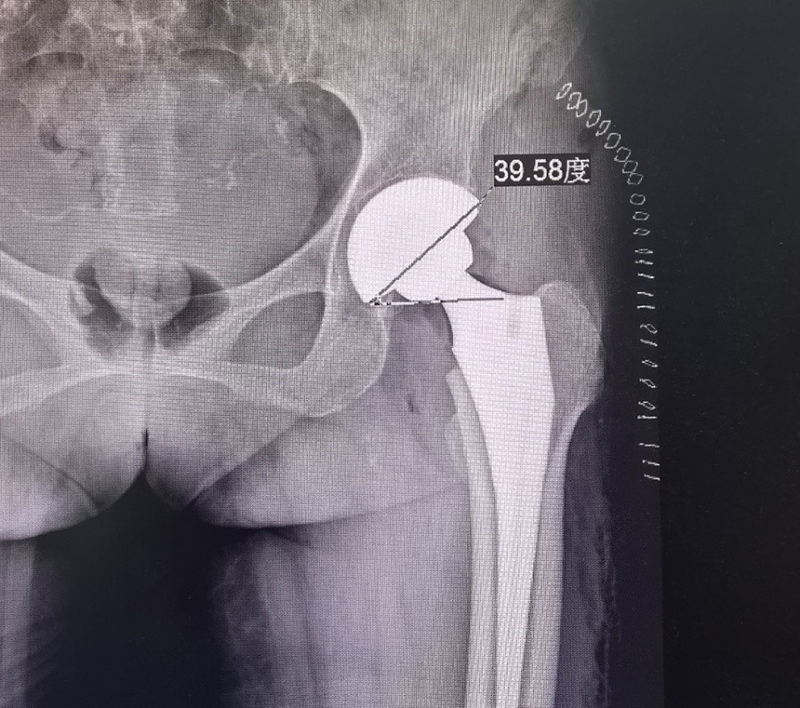

手术分别进行了双侧膝关节和双侧髋关节置换,手术过程顺利,在医护人员的精心护理下,利用快速康复技术,李先生没几天就下床锻炼了,关节活动良好。手术复查片子分析和设计角度外展40度前倾20度的理想只有1度左右误差,相当精准,屈曲的关节终于舒展开来,李先生也露出了满意的笑容。

化难为易,培优奠基。目前骨科发展中数字化3D 打印技术是尖端潮流技术,如何利用高科技服务临床是目前的主要问题。在髋关节置换中最常见的并发症是手术后的脱位,如何减少预防脱位增加关节置换的稳定平衡是普遍难题。首先,髋关节解剖复杂手术中立体定位困难。其次,如果关节增生变形更容易误导手术方向,使手术安装方向出现误差,安装角度直接影响关节的稳定性,也是造成脱位的主要原因。我院骨科三区团队积极与相关技术人员组成攻关小组,利用国内高新技术设计应用3D模拟技术做出髋关节导板,引导指示手术方向,使髋关节置换中利用3D技术模拟的标志导板准确手术,精确的内外翻及外展角度能使手术安装的假体更科学,防止关节脱位,有利于功能康复恢复。该技术目前国内也极少数应用,省内尚未见报道。该技术主要针对难度大的髋关节置换具有精准指导作用,像下肢无力,偏瘫等手术更加安全有效,能够极大地缩短手术时间,减少患者痛苦和手术风险,从而达到理想的手术效果。